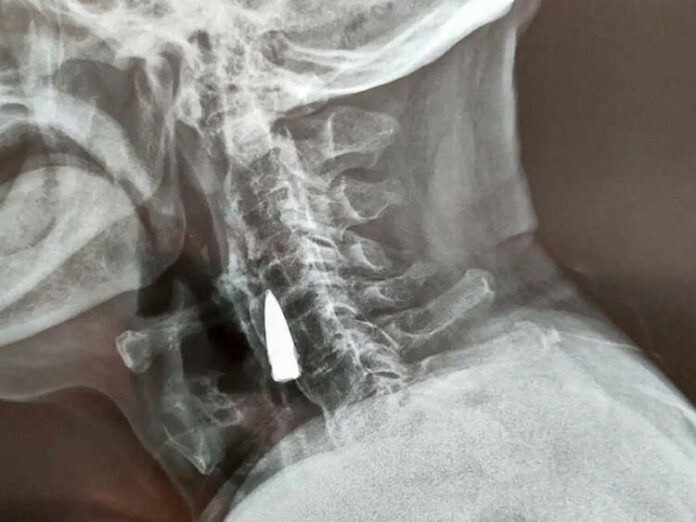

Setelah mendengar tentang kejatuhannya, dokter merekomendasikan rontgen, untuk memastikan bahwa dia tidak mengalami kerusakan serius di lehernya. Hanya alih-alih patah, sinar-X mengungkapkan adanya benda asing di leher pria itu, yang diidentifikasi sebagai peluru tua.

Zhao sendiri memperkirakan peluru itu sudah ada di lehernya sejak tahun 1944, ketika dia terkena peluru saat menyeberangi sungai. Peluru diduga masuk melalui sisi kiri hidung, melubangi rahang atasnya dan merontokkan giginya sebelum bersarang di lehernya. Ini hanya firasatnya.

Setelah memeriksa X-ray, dokter memberi tahu Zhao He dan keluarganya bahwa peluru itu dekat dengan beberapa pembuluh darah utama dan karena itu tidak menyebabkan masalah apa pun, lebih baik membiarkannya. Veteran perang itu pun setuju.